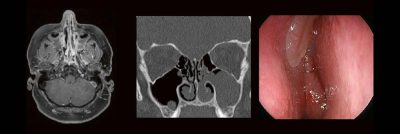

Dr. med. André ReisbergDr. med Sebastian Plößl Die bildgebende HNO-Diagnostik macht es Anfängern nicht leicht. Die Anatomie ist komplex und weniger intuitiv als in anderen Körperregionen. Normvarianten erschweren insbesondere in den Nasennebenhöhlen den Lernprozess. Sobald pathophysiologische Zusammenhänge verstanden und wichtige klinische Aspekte verinnerlicht wurden, gelingt es einen praxistauglichen, belastbaren Befund zu erstellen. Wo muss ich eigentlich hinschauen? Was will der […]